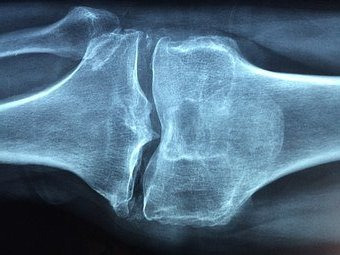

2. 반월상 연골 파열

정강이 주변의 C자 모양으로 된 반월 연골이 파열되어 나타나는 반월상 연골파열은 발생 후 퇴행성 관절염으로 이어지기 때문에 평상시 주의가 필요합니다.